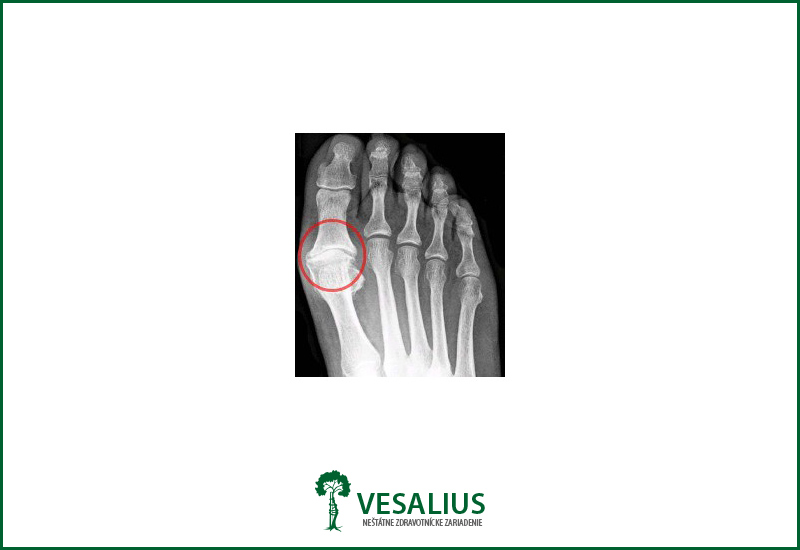

Je to stav sprevádzaný bolestivosťou v oblasti I. predpriehlavkovo-palcového kĺbu spôsobený jeho artrózou – „opotrebovaním“. Dochádza ku obmedzeniu hybnosti v tomto kĺbe a výraznej bolestivosti pri chôdzi, najmä v mäkkých topánkach, preto pacient chodí po vonkajšej strane chodidla. V oblasti kĺbu najmä na zadnej časti môžeme nahmatať kostné výrastky, niekedy vzniká zapálená burza v mieste najväčšieho tlaku.

Vykonávame operáciu podľa Kellera ( pozri hallux valgus) a dopĺňame znesenie kostných výrastkov na kostiach – na hlavičke prvej predpriehlavkovej kosti a bližieho článku palca. Po operácii sa nenakladá sádrová dlaha.